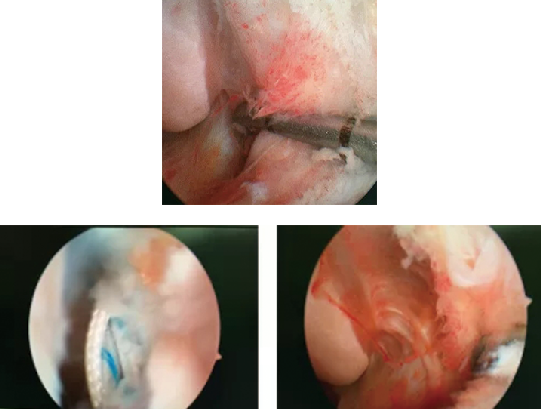

完善相关检查后,石院长徐主任手术团队为患者进行了关节镜下韧带修复术和机器人辅助下骨折固定术。首先利用踝关节镜探查距腓前韧带断裂,用可吸收带线锚钉修复;镜下探查复位保证距骨关节面平整;由机器人定位,精准地闭合平行打入两枚空心螺钉,骨折固定精准稳定。

整台手术完成时间不到2小时,手术时间缩短,手术微创性和精准性却大大提高。机器人为螺钉的置入提供精准的空间定位和稳定的路径,由于置入精度高,误差在0.8mm以下,在距骨形状复杂,螺钉通道狭长的情况下,准确实现了预定的内固定方案。

而传统的双侧大切口有利于充分显露复位骨折,直视下置入螺钉,但会加重距骨血供破坏,术后易出现骨不愈合、距骨坏死等并发症;但在骨科手术机器人的辅助下,可以实现体外精确定位不需要直视下置入螺钉,切口明显变小,减少了损伤,大大地减少了并发症。

踝关节解剖结构复杂,疾病多种多样。踝关节镜是近年来兴起的一种踝关节疾病和创伤的微创治疗技术,通过2个0.5cm切口,将镜子伸到踝关节一个切口内,等于把术者的眼睛延伸到了患者体内;另外一个切口伸入特制器械来进行操作,大大减少了开放手术带来的创伤和并发症。随着器械的发展和人们对疾病的深入认识,踝关节镜的适应症越来越广泛。